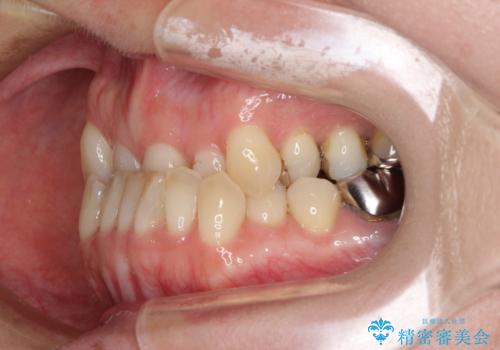

- 前歯の反対咬合を気にして来院された患者様です。

上顎骨の幅が下顎骨よりも小さいので、拡大装置により骨幅を広げて上下関係を改善すると同時にワイヤー矯正で反対咬合の改善を図り、その後インビザラインにて歯並びを整えることとしました。

上顎前歯の矮小歯は矯正治療の途中でオールセラミッククラウンを装着し、左右のバランスを整えることとしました。

急速拡大装置の使用により奥歯の咬み合わせが劇的に変わり、その変化を利用して反対咬合を改善することができました。

治療期間中は奥歯が咬み合わず、食事が取りにくいなどの不都合がありましたが、最終的にはきれいに整えることができました。